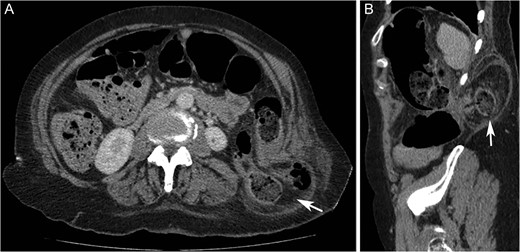

On examination, there was a 15 cm, irreducible, mildly tender lump in the left superior lumbar triangle, in the region of previous lipoma excision. There were audible bowel sounds on auscultation of the lump. No other swellings of the abdominal wall were identified and the patient was not known to have any hernias. Abdominal radiograph revealed faecal loading in the ascending colon with dilated large bowel loops (Fig. 2). Subsequent computed tomography (CT) scan showed a left superior lumbar triangle hernia containing a loop of colon (Fig. 3) with dilated large bowel proximal to this, in keeping with obstruction.

Abdominal supine plain radiograph showing faecal loading in ascending colon and dilated large bowel loops in a 72-year-old woman diagnosed with large bowel obstruction secondary to left sided superior lumbar triangle hernia.